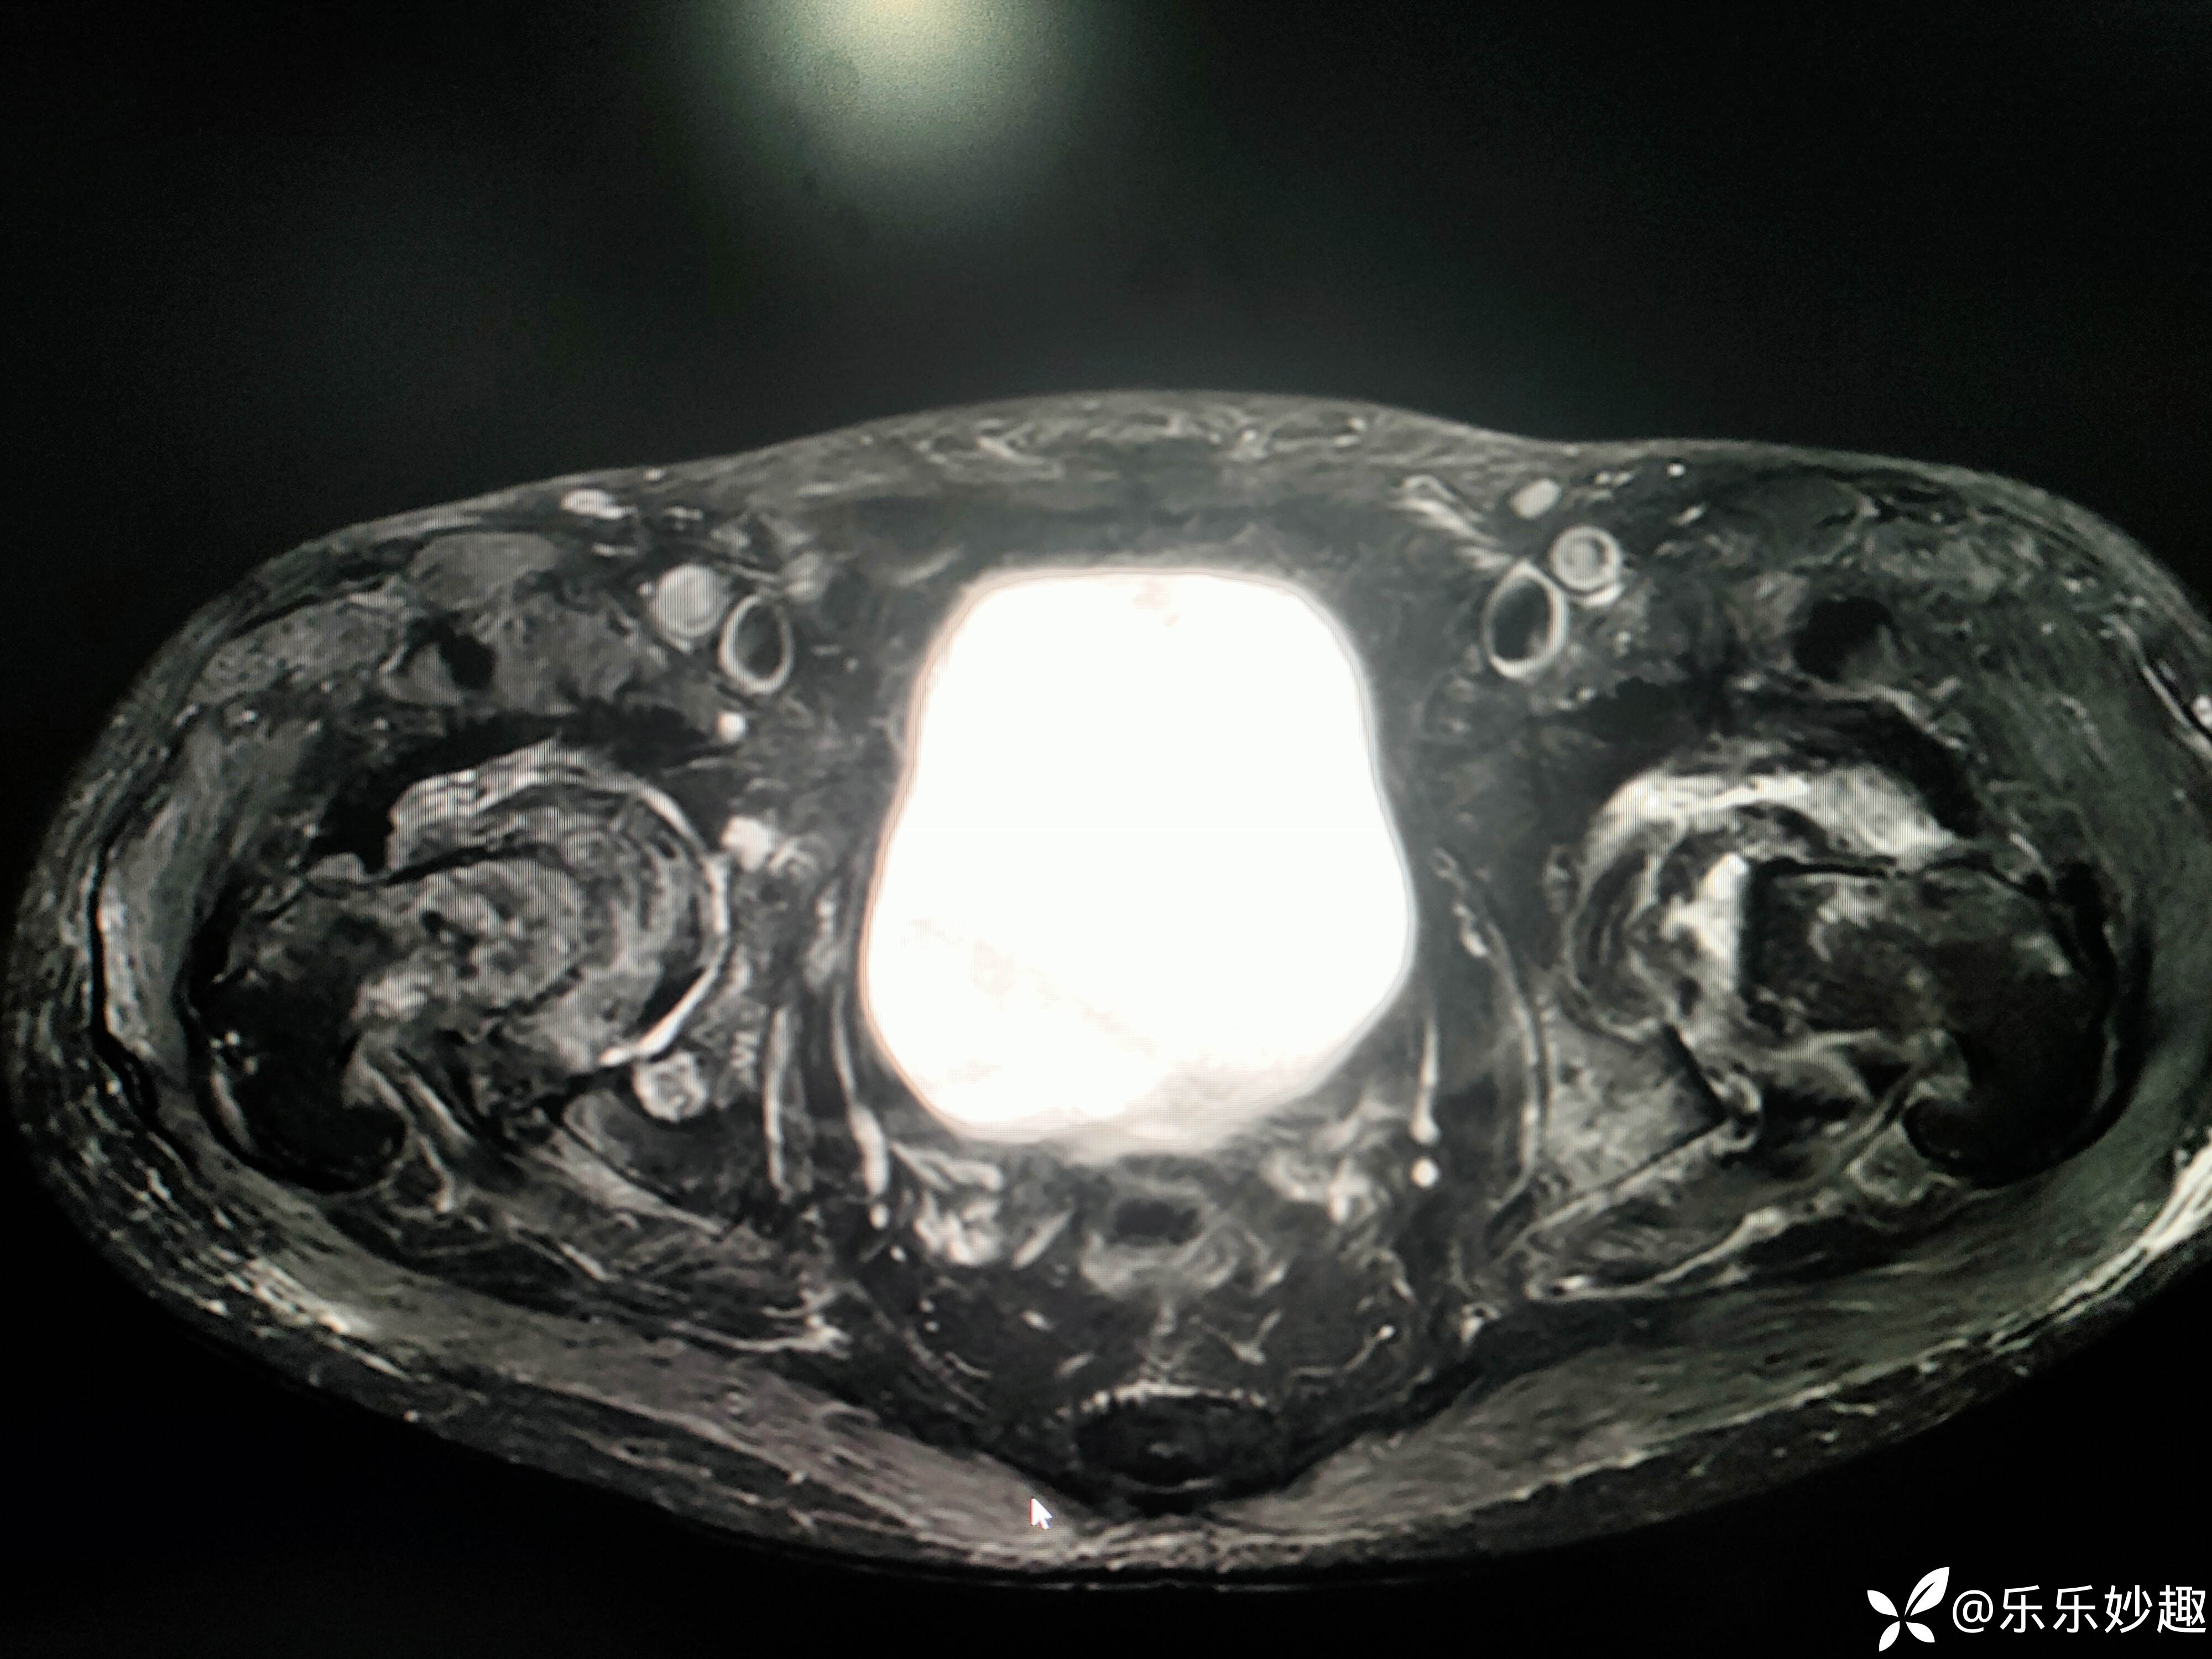

最后做了髋关节MR,见下图